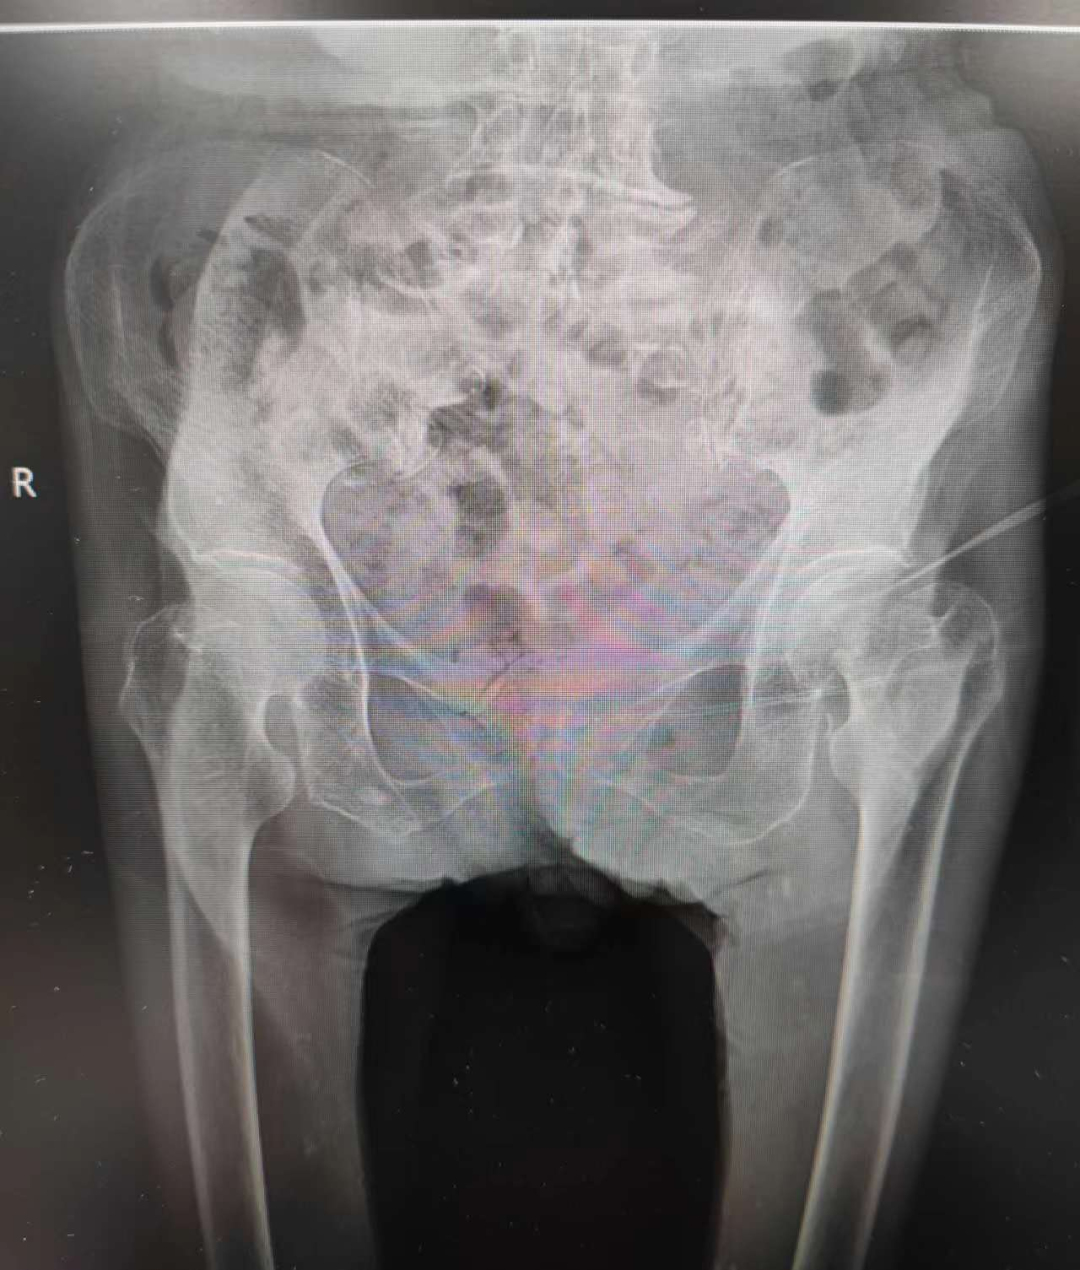

术前DR片显示左股骨颈骨折